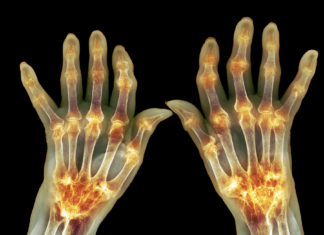

Artrite reumatoide: nanoparticelle per ridurre le riacutizzazioni

L’artrite reumatoide è una patologia autoimmune cronica attualmente non curabile: i trattamenti si focalizzano su gestione dei sintomi e rallentamento della progressione, senza però prevenirne l’insorgenza o evitarne le dolorose riacutizzazioni.